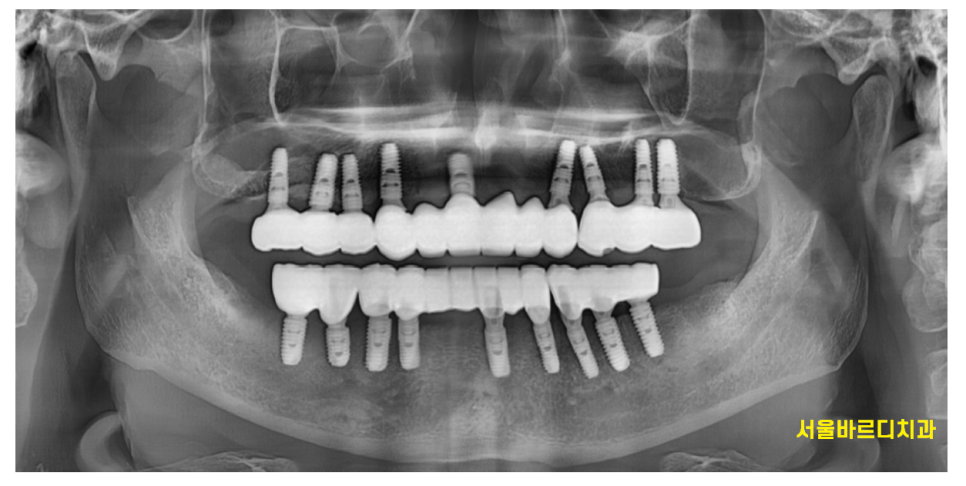

240904

같은 분이라는 게 느껴지시나요??

다음번에는 전악 임플란트로 치료해드린 이야기를 해드릴겁니다.